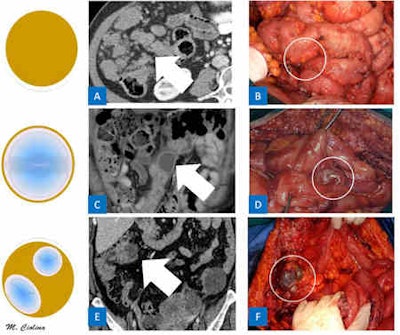

Ciolina wrote that peritoneal carcinosis is characterized by the presence of neoplastic implants with different morphological features and distribution in the peritoneal cavity. Radiologists must evaluate both morphology and localization. Solid, cystic, and mixed implants can present with different patterns that depict typical aspects of peritoneal carcinomatosis.

The micronodular pattern is characterized by the presence of tiny 1- to 5-mm milky spots of peritoneal implants diffusely involving the tunica serosa and subserosal fat. The greater omentum, lesser omentum, and mesentery are typically involved. Conversely, the nodular pattern is characterized by the presence of nodular implants larger than 5 mm diffusely involving the tunica serosa and subserosal fat. Nodules may have an oval shape with rounded contours or a star shape appearance with spiculated margins providing a stellate pattern, she pointed out.

In ovarian carcinomatosis, CT can demonstrate subtle nodularity and stranding of the mesentery and more apparent nodularity along the greater omentum. On the other hand, gastric carcinoma with diffuse gastric wall thickening has a linitis plastica appearance on CT.